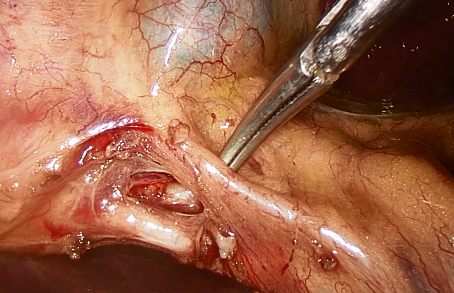

Se realizó evacuación de vesícula patológica por punción con aguja obteniendo hidrocolecisto. Se procedió a disección de triangulo de Calot, identificando primera arteria cística que se secciona entre clips de titanio dos en sentido proximal y uno distal (LT300 verde Johnson & Johnson) (ver imagen 4).

Imagen 4: Disección de arteria cística.

Identificación de dos conductos císticos, que se disecan y separan entre sí, ambos con destino a cuerpos vesiculares por separado, objetivando unión cístico-bacinete de los mismos (ver imagen 5).

Imagen 5: Identificación y disección de los 2 conductos císticos (flechas blancas) con destino a cuerpos vesiculares separados (cruces blancas); unión cístico-bacinete (flechas azules) de ambos conductos.